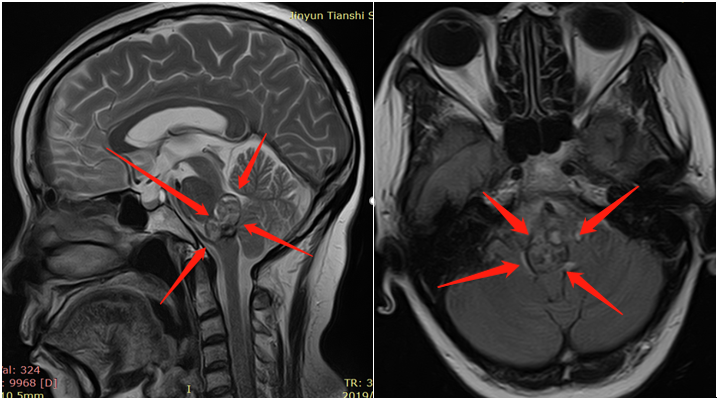

近几十年来,随着磁共振成像(MRI)在临床实践中的广泛应用,脑海绵状血管瘤(CCM)的发病率有所上升(0.4-0.9%)。 脑干海绵状血管瘤 占全部颅内海绵状血管瘤的...

脑干海绵状血管瘤引起的脑干出血需要手术吗?海绵状血管瘤是指长在脑内的血管畸形,其中脑干部位的海绵状血管瘤是预后较差的颅内海绵状血管瘤,手...